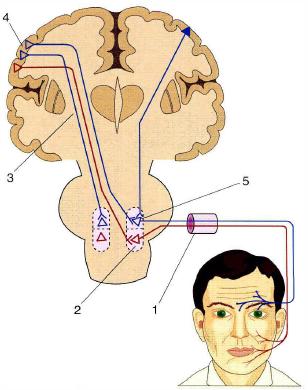

Пирамидная симптоматика в неврологии: ключевые аспекты